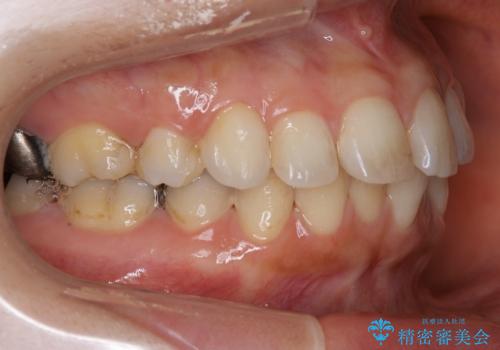

前歯のガタつきを改善 抜歯矯正後の後戻り

- 抜歯矯正後の後戻りで前歯ガタつきが主訴で来院された患者様です。

後戻りの程度としては軽度なので、治療期間としては短く終えることが出来ました。

前歯の正中線も改善され大変満足して頂きました。